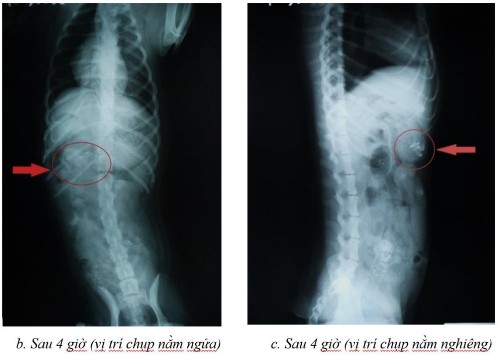

Một số dữ liệu đánh giá sự dịch chuyển in vivo trong đường tiêu hóa chó bằng phương pháp hình ảnh x-quang

Phụ lục 5.1. Hình ảnh X-quang chó 2 ở thời điểm (a) sau 2 giờ ở vị trí nằm nghiêng, (b) sau 4 giờ ở vị trí nằm ngửa, (c) sau 4 giờ ở vị trí nằm nghiêng, (d) sau 7 giờ ở vị trí nằm ngửa, (e) sau 7 giờ ở vị trí nằm nghiêng, (f) sau 9 giờ ở vị trí nằm ngửa, (g) sau 9 giờ ở vị trí nằm nghiêng, (h) sau 11 giờ ở vị trí nằm ngửa và (i) sau 11 giờ ở vị trí nằm nghiêng